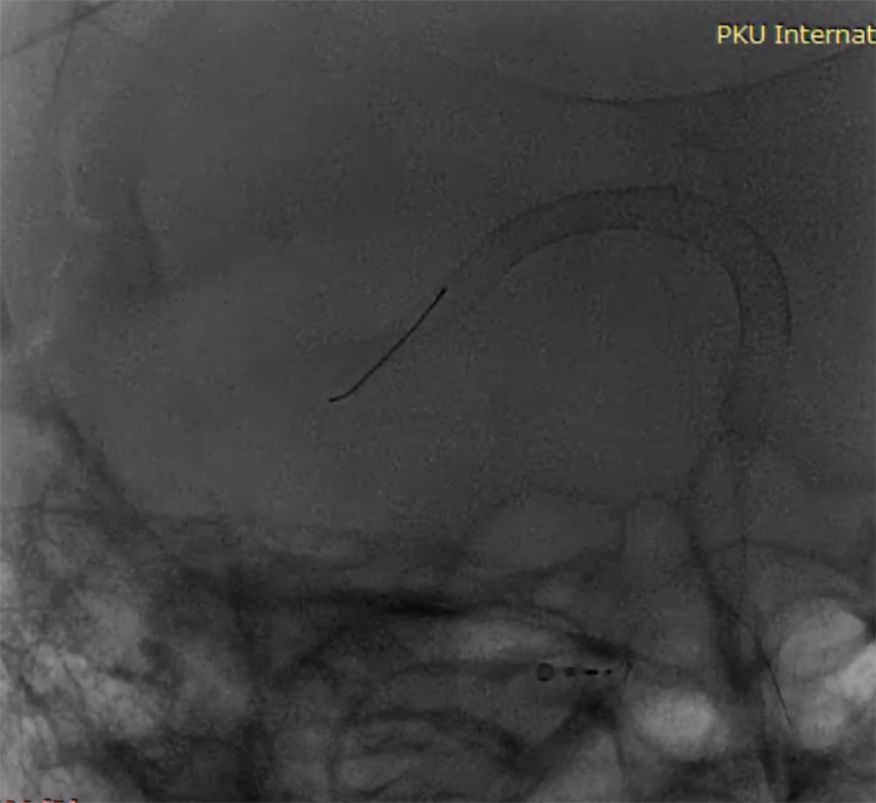

(2)左颈动脉造影见大脑前动脉抬高,右侧颈内动脉球囊闭塞试验见前交通动脉开放,M1段显影不良,考虑后交通供血较强(图2)。

图2

(3)后循环造影及右侧颈内动脉球囊闭塞试验,提示后交通供血较明显,可见动脉瘤显影,无法闭塞颈动脉,选择行动脉瘤栓塞术(图3)。